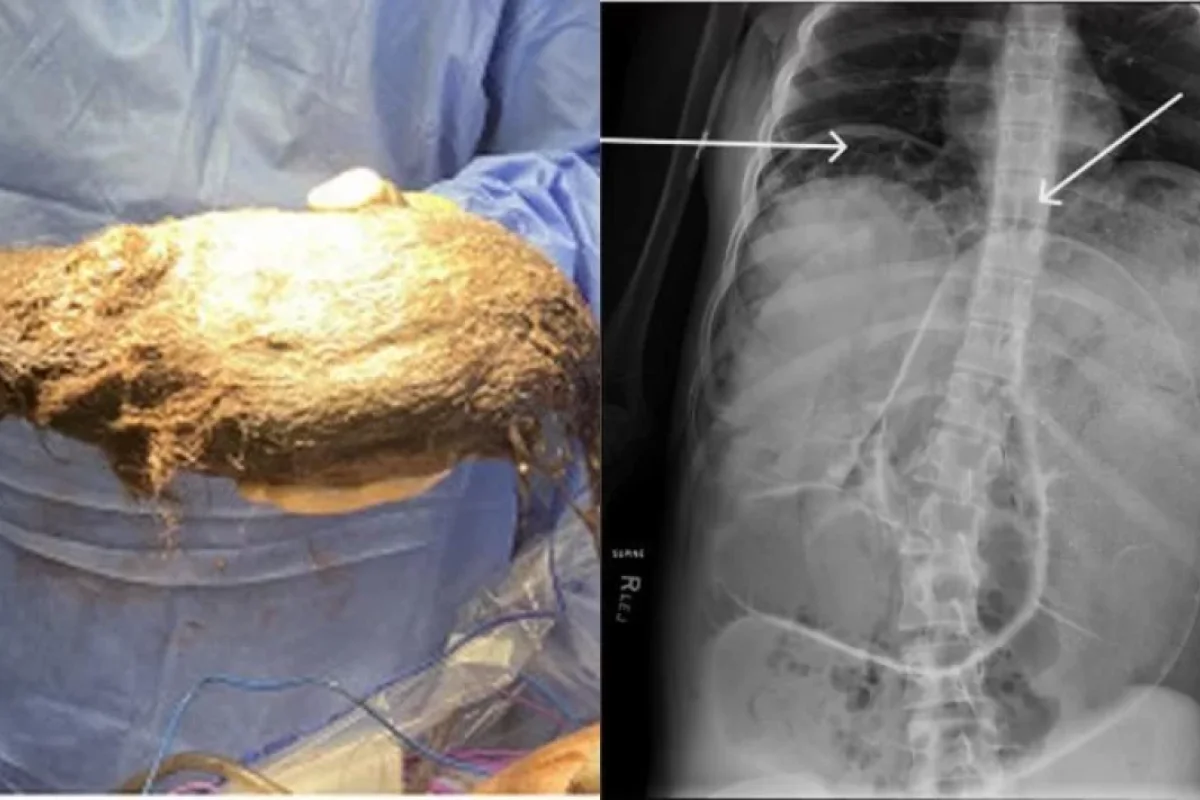

News24.az bildirir ki,  qızın mədəsindən 2,5 qramlıq tük kürəsi çıxarılıb. Həkimlər bunun "Rapunzel sindromu" olduğunu deyiblər.

Şoka düşən həkimlər mürəkkəb prosedurdan sonra qızın mədəsindən çəkisi 2468 qram olan tük kürəsini çıxarıblar.